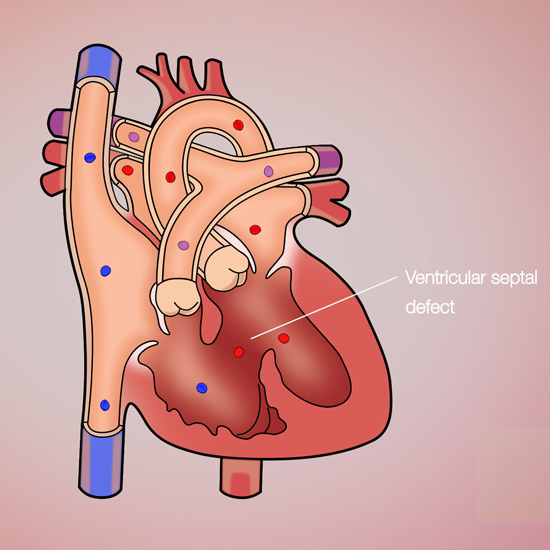

Treatment Of Ventricular Septal Defect (VSD) which is a defect in the ventricular septum,